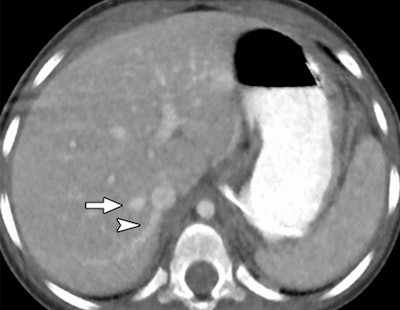

Reduced-dose axial CT images reconstructed with MBIR (above) and 100% ASIR (below) in a 30-month-old girl with a history of a malignant germ cell tumor in the right hepatic vein (arrow) and an accessory right hepatic vein (arrowhead). Images republished with permission of RSNA from 10.1148/radiol.13130362, October 3, 2013.